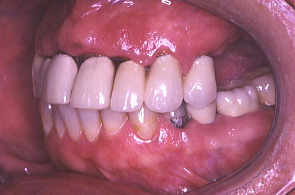

最初の写真は先にワックスで作った形を模倣して口腔内で再現し、仮り歯を作ったもの。次の写真は歯周外科を施し、深い歯周ポケットの歯垢を除去したところ。歯肉の色や艶が健康色を取り戻した。

矯正も兼ねて仮歯を修正:歯と歯の隙間を閉じる為仮り歯を修正したところ。患者は健康になり笑顔を取り戻した。日常の話やいろいろな悩みを聞いているうちに大分治療に慣れてきたように感じた。 そして物事をポジティブに考えられるようになってきたということだった。この頃から患者は体の調子を整える為、食事のダイエットを初めた。